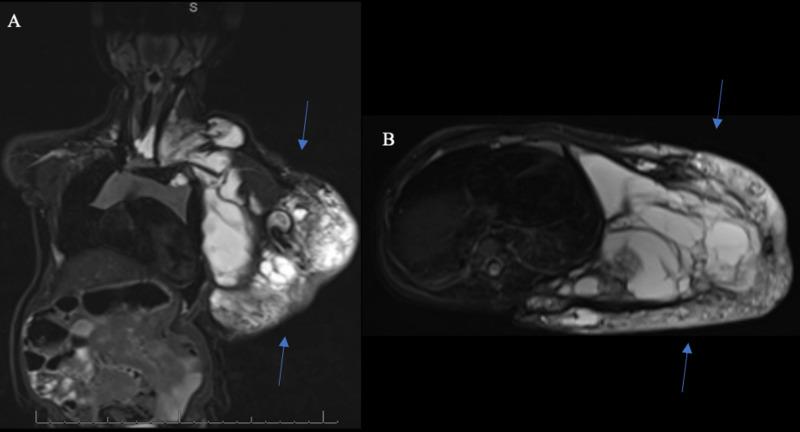

Vascular malformations are being increasingly identified with associated syndromes caused by sporadically occurring, non-heritable somatic mutations. CLOVES syndrome is a newly recognized constellation of congenital lipomatous overgrowth with vascular malformations, epidermal nevi, and skeletal/spinal anomalies. We report the unique case of CLOVES syndrome diagnosed in a pediatric patient five years after the initial surgical resection of an extensive venolymphatic malformation involving the chest, neck, axilla, and posterior trunk. The lipomatous overgrowths were successfully resected, and subsequent genetic analysis revealed a heterozygous, pathogenic, somatic variant in the PIK3CA gene, confirming our suspicion of CLOVES syndrome.

血管畸形越来越多地被发现与由散发的、非遗传性体细胞突变引起的相关综合征有关。CLOVES综合征是一种新认识的先天性脂肪瘤过度生长伴血管畸形、表皮痣和骨骼/脊柱异常的综合征。我们报告了一例独特的CLOVES综合征病例,该病例是在一名儿科患者首次手术切除累及胸部、颈部、腋窝和后躯干的广泛静脉淋巴管畸形五年后被诊断出来的。脂肪瘤过度生长被成功切除,随后的基因分析显示PIK3CA基因存在杂合性、致病性体细胞变异,证实了我们对CLOVES综合征的怀疑。